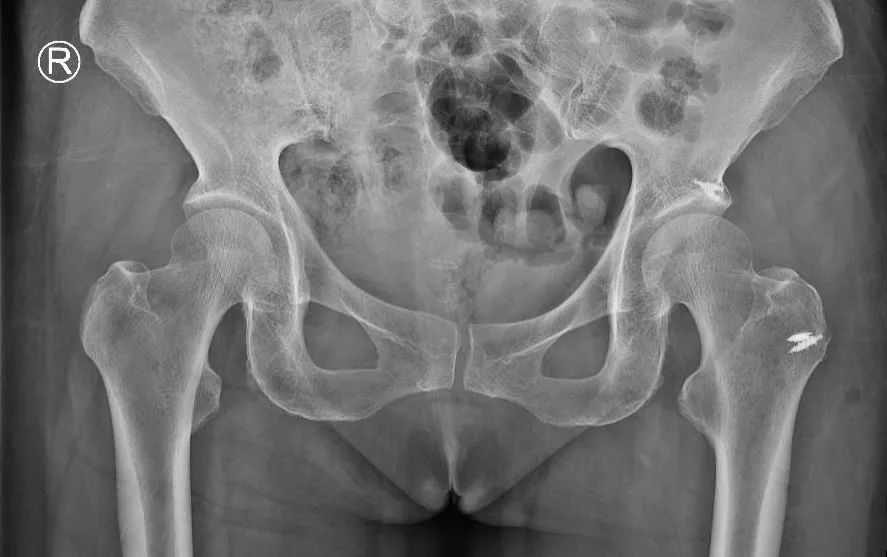

图5 术后X线

术后患者恢复良好

疼痛明显减轻

满意出院